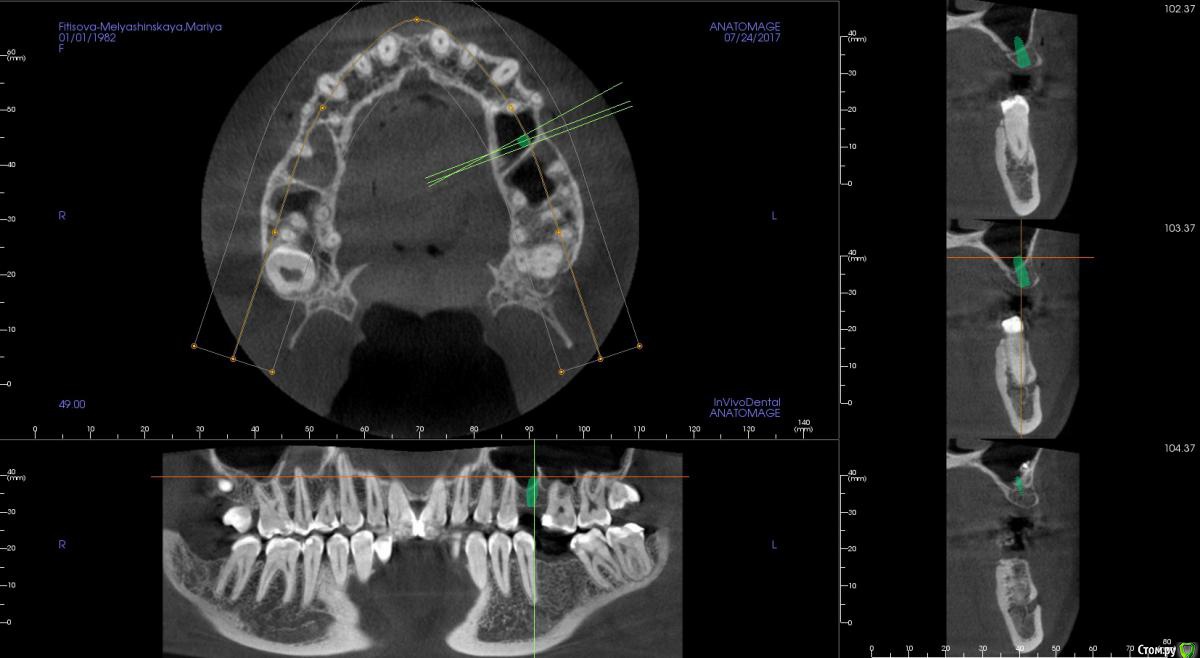

kamranchick Опубликовано 31 июля, 2017 Автор Поделиться Опубликовано 31 июля, 2017 Как то вот так получилось Ссылка на комментарий

Bobon Опубликовано 31 июля, 2017 Поделиться Опубликовано 31 июля, 2017 длина 8,5? Ссылка на комментарий

kamranchick Опубликовано 31 июля, 2017 Автор Поделиться Опубликовано 31 июля, 2017 длина 8,5?ага Ссылка на комментарий

Bobon Опубликовано 31 июля, 2017 Поделиться Опубликовано 31 июля, 2017 у некоторых производителей есть импланты длиной по 6 мм, целесообразно ли их использование или лучше не рисковать? Ссылка на комментарий

kamranchick Опубликовано 31 июля, 2017 Автор Поделиться Опубликовано 31 июля, 2017 у некоторых производителей есть импланты длиной по 6 мм, целесообразно ли их использование или лучше не рисковать?у некоторых есть и 4 мм длина, все по показаниям... Ссылка на комментарий